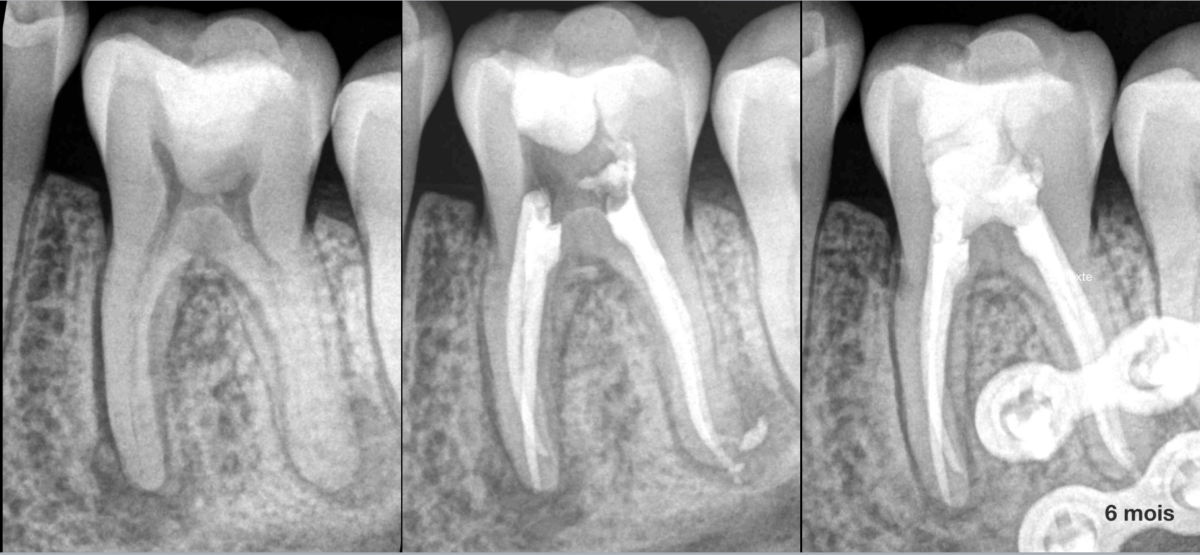

🔍 𝐐𝐮’𝐞𝐬𝐭-𝐜𝐞 𝐪𝐮𝐢 𝐩𝐨𝐮𝐫𝐫𝐚𝐢𝐭 𝐞𝐦𝐩𝐞̂𝐜𝐡𝐞𝐫 𝐝𝐞 𝐜𝐨𝐧𝐭𝐫𝐨̂𝐥𝐞𝐫 𝐥’𝐞𝐟𝐟𝐢𝐜𝐚𝐜𝐢𝐭𝐞́ 𝐝𝐮 𝐭𝐫𝐚𝐢𝐭𝐞𝐦𝐞𝐧𝐭 𝐜𝐚𝐧𝐚𝐥𝐚𝐢𝐫𝐞 𝐝𝐞 𝐜𝐞𝐭𝐭𝐞 𝐝𝐞𝐧𝐭 𝐧°𝟑𝟔 ❓

➡️ Les plaques d’ostéosynthèse d’une ostéotomie bi maxillaire !

Pour autant, on parvient à deviner la régression des lésions radioclaires et le patient est asymptomatique.